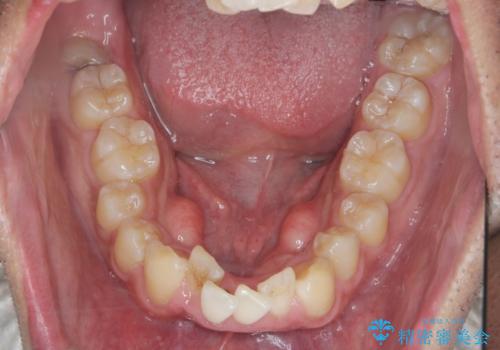

マウスピース矯正で前歯の角度、ガタガタをきれいに

- 突き出た前歯の角度、歯ブラシのしづらい前歯のがたつきの改善を希望され来院されました。

4本の小臼歯を抜きワイヤー矯正治療、下顎前歯を1本抜去しマウスピース治療のメリットデメリットを検討・相談し、より歯を抜く本数の少ないマウスピース矯正を行うこととなりました。

下顎の前歯は1本だけ抜去せざるをえませんでしたが、4本の小臼歯抜去とマルチブラケット矯正を回避することができ、治療結果・過程に満足いただくことができました。